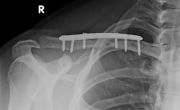

Κατάγματα Άνω Άκρων

Ορισμένες από τις περιπτώσεις καταγμάτων Άνω Άκρων που έχει αντιμετωπίσει ο κ. Παπασωτηρίου Αντώνιος.